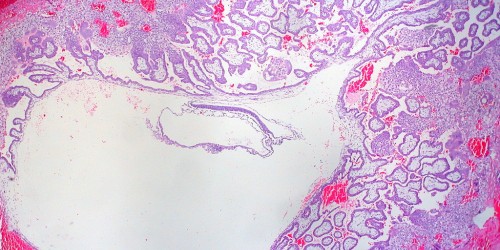

I went to the DR the other day and they said it was to early to see anythink in the uterus. but they saw a cyst like structure in my left tube and a cyst on my left ovary. im doing regulare HCG testing and hoping for the best. i was thinking that this "structure" in my tube could be an ectopic preg. what ever happened with your situation?